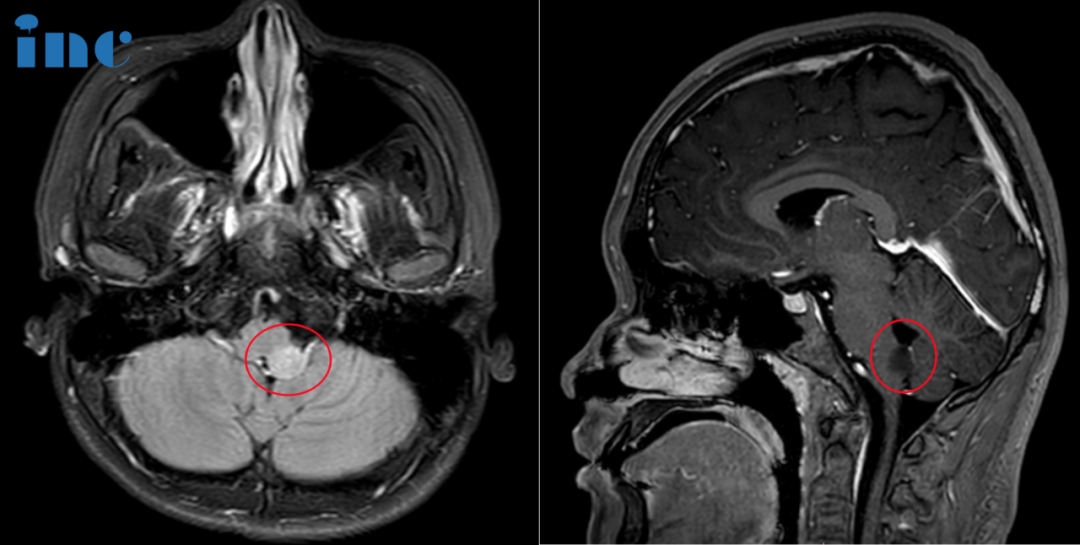

05、17岁女孩,右侧基底节,双侧丘脑及大脑脚,中脑弥漫病变,可以手术吗?

病史摘要:杨先生没想到,17岁的女儿媛媛竟然会得这样的重病。他恨老天的不公,2023年7月底,媛媛出现无明显诱因的头晕呕吐,检查结果正常。到了8月中旬,媛媛母亲观察发现患者左下肢有无力现象,左上肢也有无力现象,此情况至目前已持续时间约15~25天。2023年8月在当地多家医院进行MR脑部检查,均诊断发现脑部右侧基底节区出现占位灶累及中脑,右侧大脑脚。考虑肿瘤性病变,生殖细胞瘤或胶质瘤可能。杨先生起初准备让女儿进行穿刺活检,但听医生说因为肿瘤位置深,穿刺风险也很大。他犹豫了,担心穿刺活检会让女儿情况加重。因为孩子目前除了左上肢无力,左脚走路拖地以及轻微的左侧面瘫症状外,其他都还正常。在得知巴教授9月来华的消息后,他希望能够请他为孩子手术切除肿瘤。

INC巴教授远程评估意见:

这是一个很复杂的病例,因为病灶位于并延伸到基底神经节内。MRI显示病变有占位效应,但没有增强对比,也没有清晰的特征来帮助我们了解这是哪种病变。我不能确定患者是否有肿瘤,因为病变确实也可能对应于局部炎症(不管是什么原因),可能是淋巴瘤或其他。

所以,在这种情况下,我不能提供手术,因为(病灶)位置深,即使活检似乎也很危险,至少对于开颅来说。可能会导致严重的运动障碍,甚至可能导致更多的神经问题。

下一步的治疗可以分两步进行:

1)从短时间(几天)的高剂量类固醇药物开始,然后进行MRI复查(在一些炎症或淋巴瘤中,MRI已经可以看到效果);

2)可能得话进行立体定向活检,这比开放式手术活检在该案例中更有指示性。